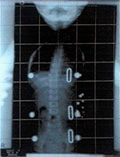

平成20年8月11日

装具して10度

レントゲン平成20年8月11日 レントゲン平成21年2月25日 レントゲン平成21年10月21日